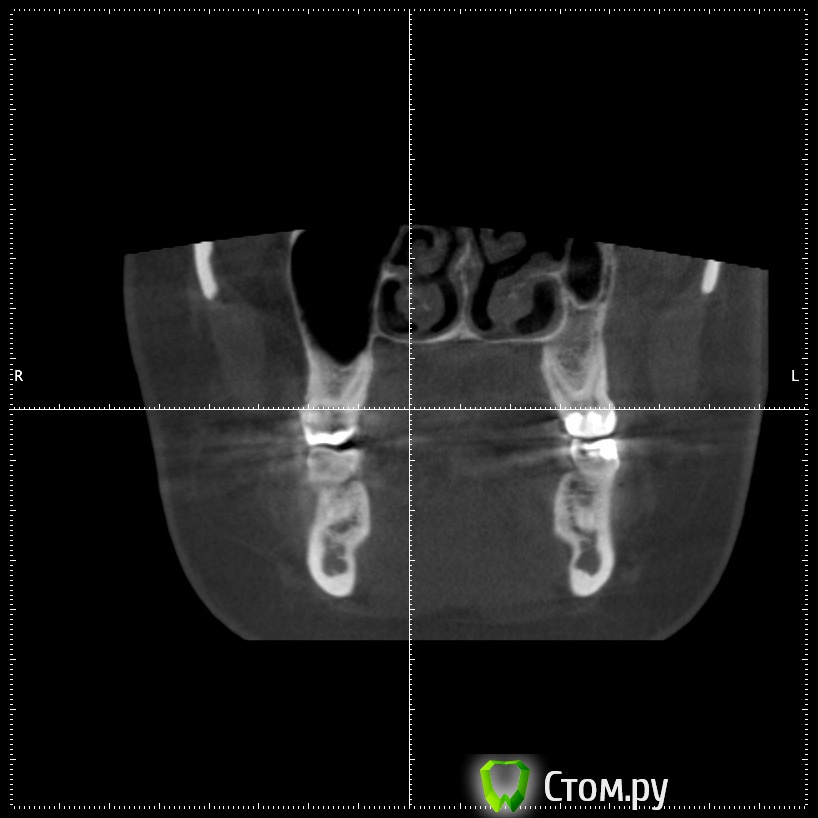

stommm Опубликовано 17 сентября, 2014 Поделиться Опубликовано 17 сентября, 2014 Всем доброго времени суток) Ко мне обратилась пациентка с жалобами на отсутствие зубов во втором сегменте. Сделала кт. Честно говоря такого кт я еще не видел.Что это, господа, вариант нормы или признак патологии? Встречалось ли подобное в вашей практике? Планирую нарастить по ширине и имплантировать, без синуса. Ссылка на комментарий

Bier Опубликовано 18 сентября, 2014 Поделиться Опубликовано 18 сентября, 2014 тут просто пазуха заросла костью, природа сделала синуслифтинг )) 2 Ссылка на комментарий

stommm Опубликовано 18 сентября, 2014 Автор Поделиться Опубликовано 18 сентября, 2014 По данным литературы, в 7-10% случаев может наблюдаться асиметрия пазух (пневматизированная/склерозированная)Я думаю здесь не просто одна пазуха более пневматизированная чем иная. Полость носа тоже кажется довольно несимметричной. тут просто пазуха заросла костью, природа сделала синуслифтинг ))А то что ширина самих пазух отличается сильно, это нормально? Ссылка на комментарий

Alexey Doc Опубликовано 18 сентября, 2014 Поделиться Опубликовано 18 сентября, 2014 Гипоплазия левой гайморовой пазухи. У самого было 2-е похожих пациентов 2 Ссылка на комментарий

dr-krasnov Опубликовано 6 октября, 2014 Поделиться Опубликовано 6 октября, 2014 Гипоплазия левой гайморовой пазухи. У самого было 2-е похожих пациентов Верный ответ. 1 Ссылка на комментарий